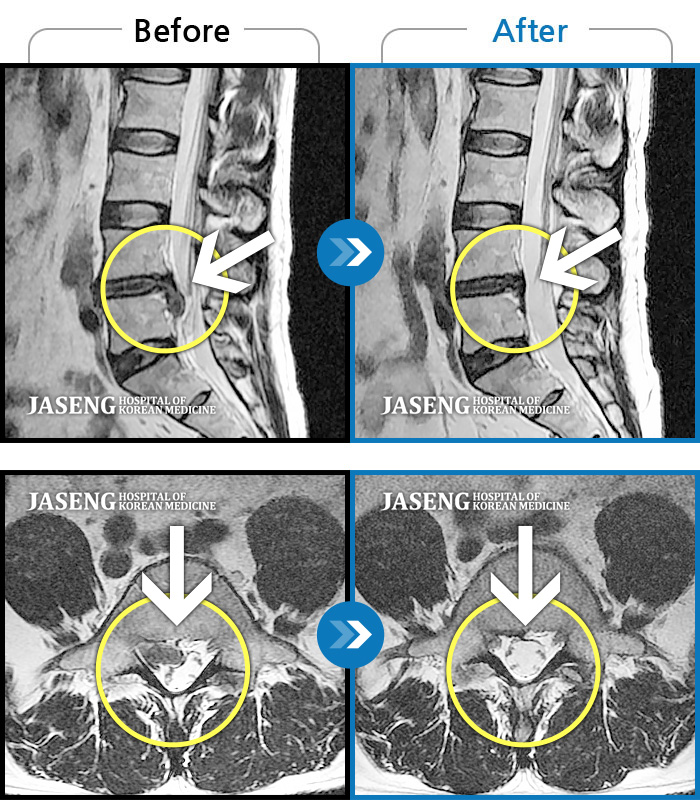

저는 척추협착과 전방위 증으로 10분도 못 걸었습니다

마지막이다 생각하고 선택한 일산 자생병원 이었습니다.

그래서 병원에서 선택한 김태용 원장님 이었습니다.

처음 뵈었을때 웃음 가득한 얼굴로 제 아픈 증상과 치료법에 대한

질문을 차근 차근 말씀 해주시며 한번 해봅시다. 하시는데 믿음갔습니다.

지금 4개월째 다니고 있는데 항상 한결 같이 웃음으로 답해 주시고

열심히 침과 약침 을 놓아 주셔서 지금은 그래도 걷는데 전보다는 많이 나아진 상태로

침을 맞으러 다닌답니다.

처음엔 몇 발작도 못가 주저 앉고 싶은 통증이었는데 지금은 계단도 잡지 않고 걸을수 있으니

얼마나 감사한지 모른답니다.